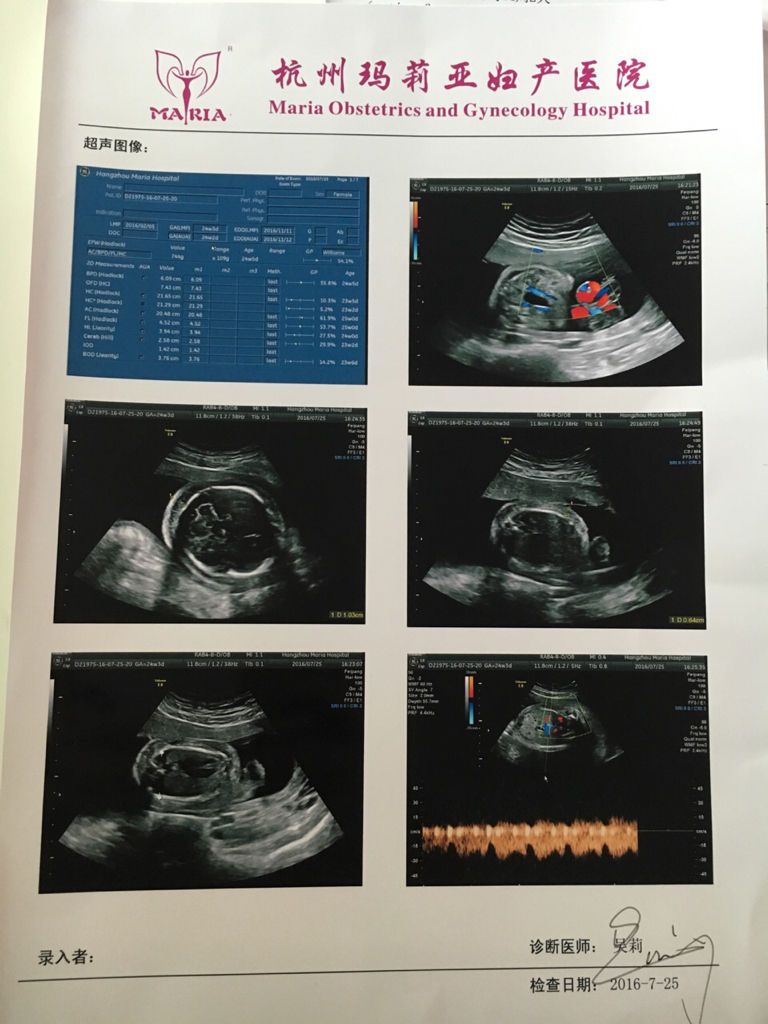

谁知道胎儿水肿,胸腔积液,怎么弄?怎么能挂到省妇保的号 谁知道胎儿水肿,胸腔积液,怎么弄?怎么能挂到省妇保的号昨天做了四维E8结果是胎儿水肿,皮肤增厚,胸腔积液, 医生建议去省妇保去看, 可是挂不到号,怎么办 点击展开 安妮爱大苹果 2016-07-26 19:19 满意回答 后排沙发 植向秋_nXYc 2016-07-26 21:50 宝宝知道提示您:回答为网友贡献,仅供参考。 为您推荐: 其他回答 花多些钱找挂号黄牛挂号肯定得。希采纳。 匿名用户 2016-07-26 19:22 相关问题 八个月胎儿头部水肿胸腔积液该怎么办 请问我刚发现自己怀孕,有流血,上周去省妇幼妇保科看的,感觉医生不好,目前在吃保胎灵,这周打算去复查,该挂哪个科室阿